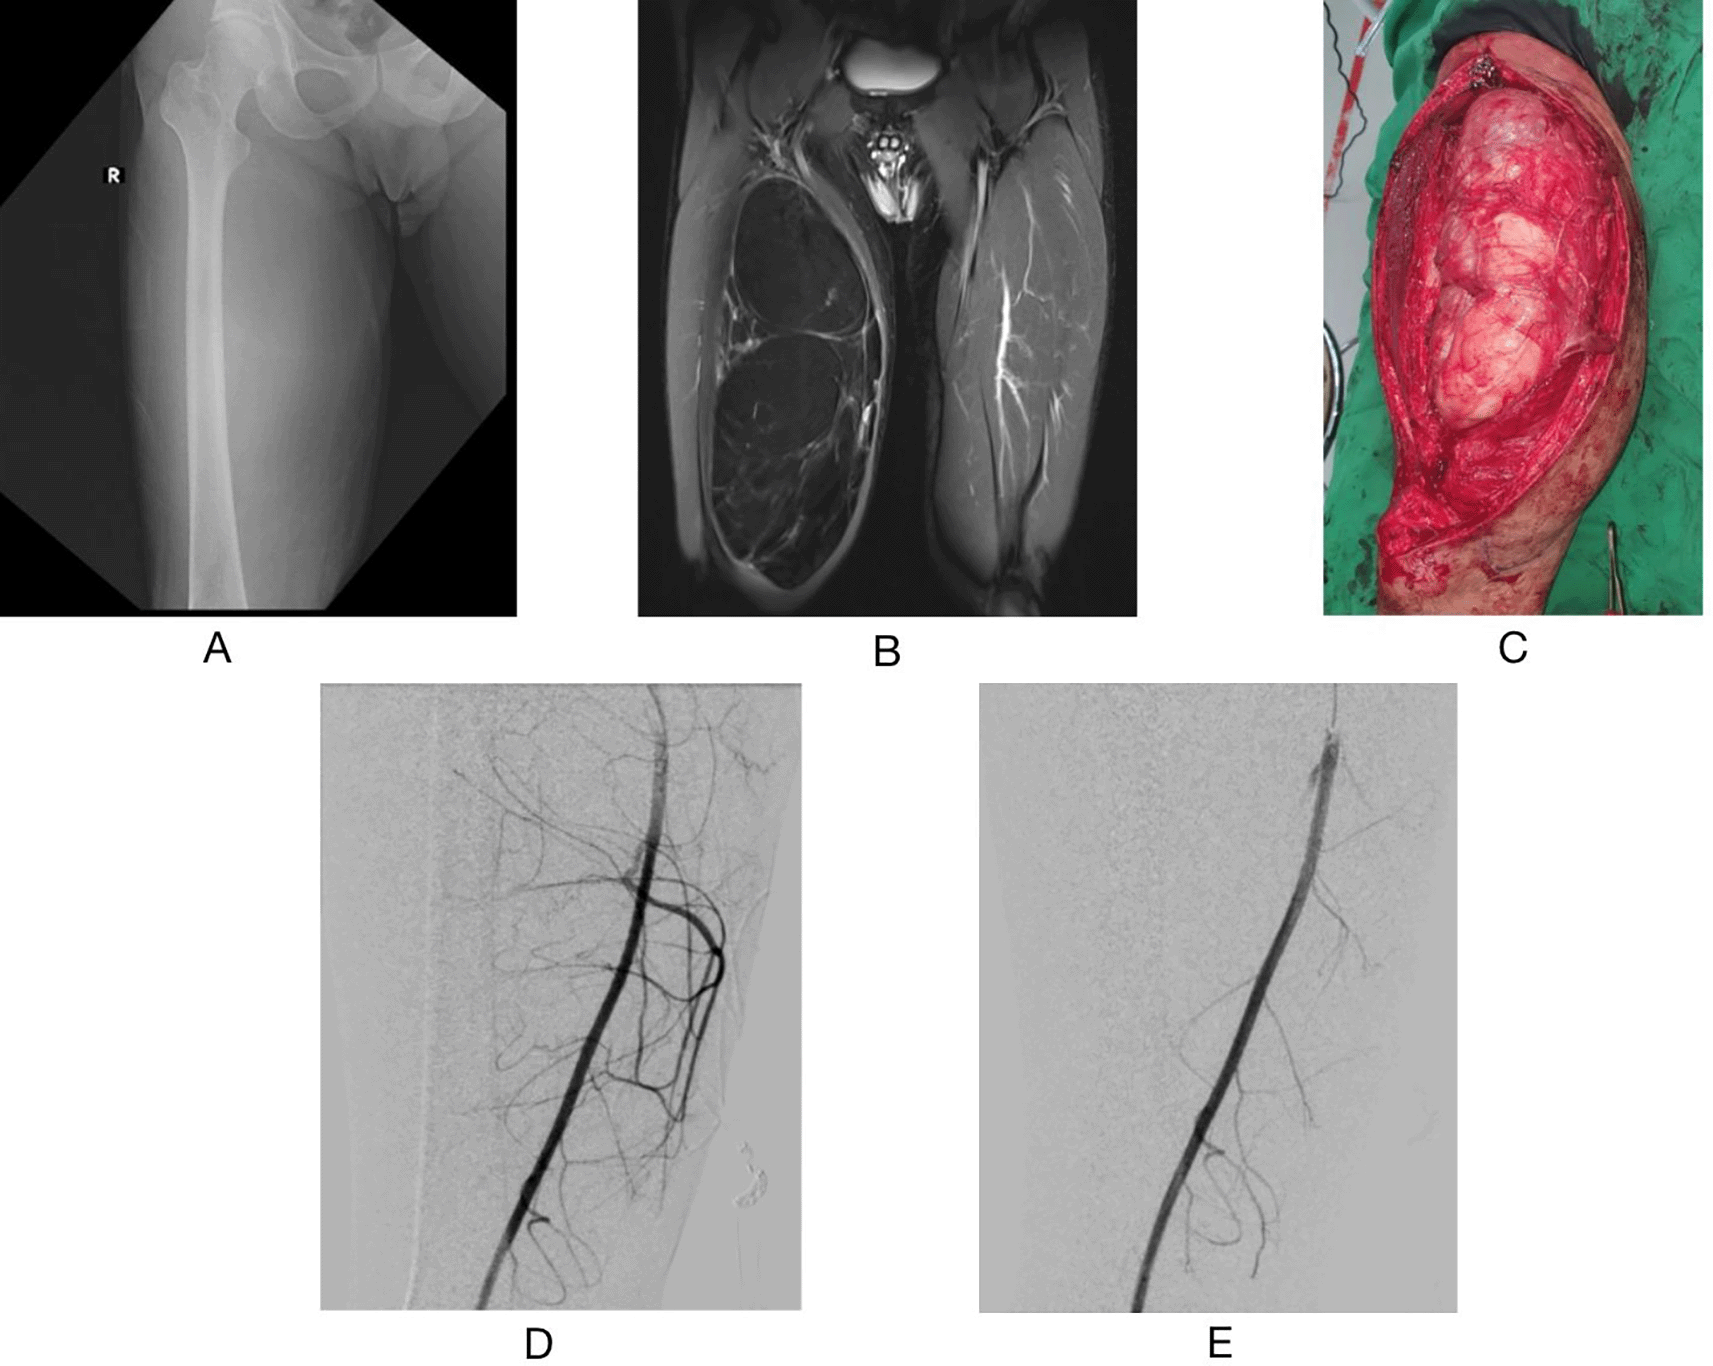

A 53-year-old man was referred to the Interventional Radiology department for preoperative endovascular embolization a day before resection of a giant right femoral mass. The mass measured 30 × 17 cm and was located along the right femur. Preoperative MRI examination revealed a 30x17 cm soft-tissue mass with a fat component located intramuscularly in the vastus medialis right femur, encasing the great saphenous vein, with no infiltration to the bone. During the procedure, a hypervascular tumor stain with a feeding artery from the superficial femoral artery was observed. Hypervascularity was absent following embolization with vertebral catheters, Progreat®, and Gelfoam®. Tumor resection was performed a day after the procedure, with only 100 mL of bleeding. The patient was then discharged seven days following after surgery. Histopathological examination revealed an atypical lipomatous tumor. Six months afterward, no recurrence was observed (Figure 2).

(A) preoperative right femur X-ray AP Position (B) preoperative T1- weighted Fat Suppressed MRI with Gadolinium contrast administration coronal view (C) Intraoperative picture (D) angiography before procedure (E) angiography after embolization procedure.